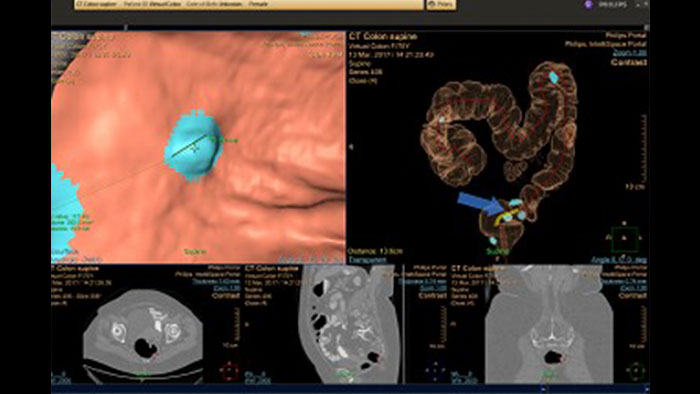

Automatically detect potential polyps in CT colonography exams

VC VeraLook CAD* uses image processing and pattern recognition technology identify colon polyps in CT colonography images, which can help streamline the reading process and improve workflow for radiologists while supporting accuracy, consistency and productivity in colon cancer screenings. Indicated for use as a second read, VeraLook is designed to enhance clinician accuracy and efficiency.

Reducing reading times in virtual colonoscopy

Enables 3D visualization of colon scans. The application automatically segments the air-filled colon and displays a calculated navigation path. The Perspective Filet view provides a synchronized display of the full colon surface wall with a single unidirectional view, reducing the need to review in both directions.